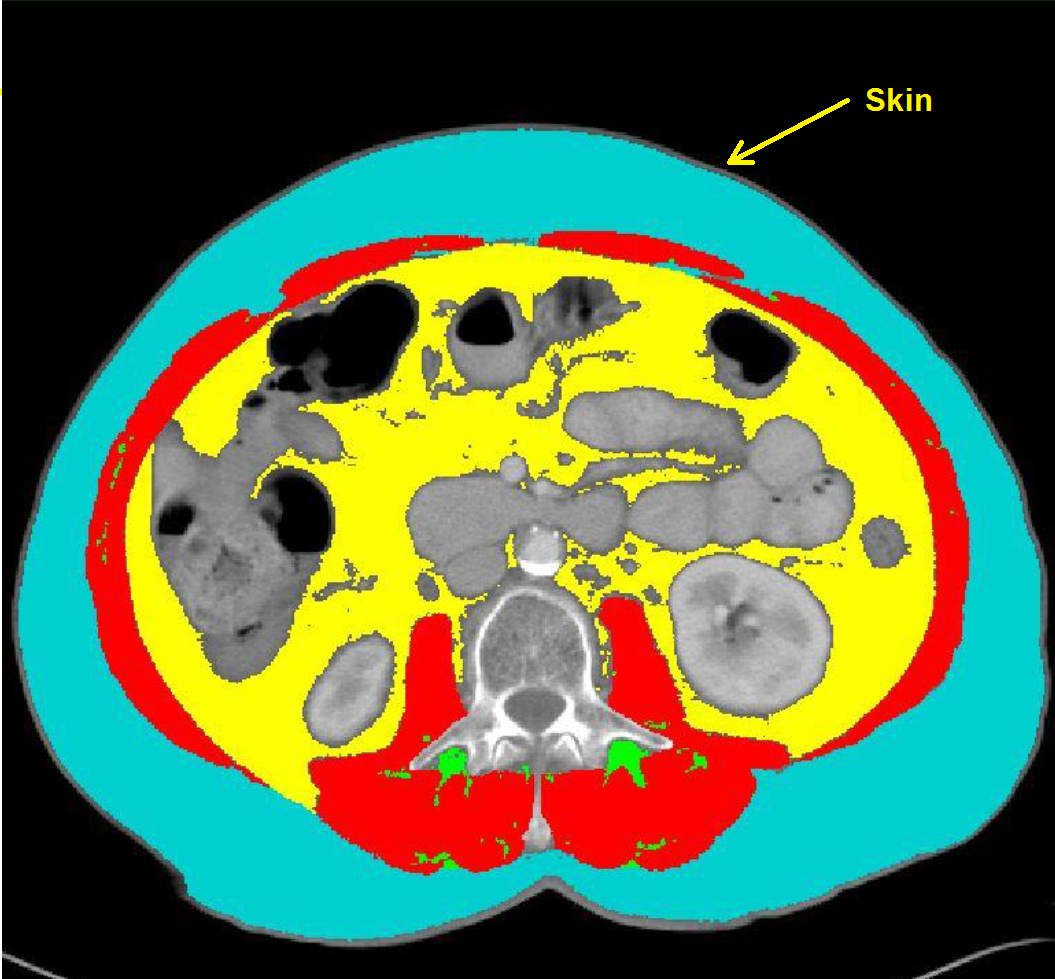

·SAT is the adipose tissue between the muscle and the skin (HU range -190 to -30) colored with TAG 7 (Cyan)

Note: ensure that the skin is not analyzed as SAT. However, the adipose tissue all the way to the skin needs to be analyzed.